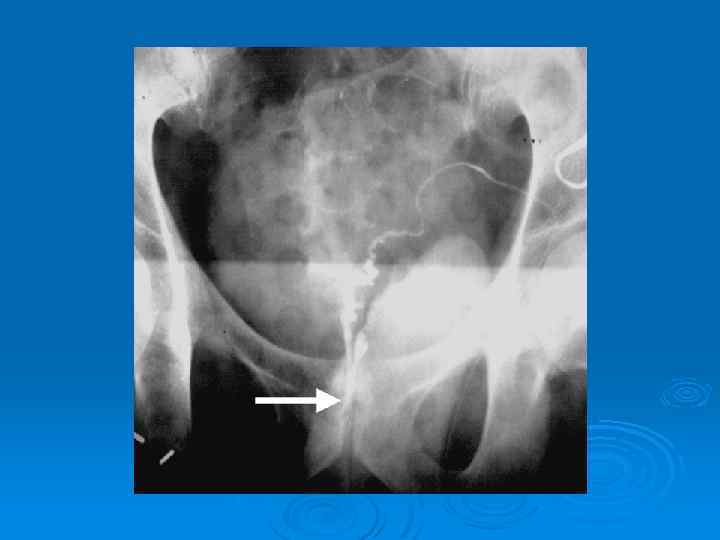

Флебография

варикоцеле